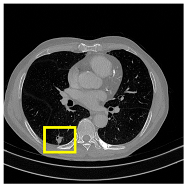

3.4.2. Representative Cases with Segmentation Challenges on the MEF-PN35 Dataset

To complement the quantitative evaluation, we present a set of representative cases from the clinical dataset that exhibited typical segmentation challenges. These cases were selected to reflect diverse morphological characteristics observed in pulmonary nodules, such as spiculated boundaries, small size, vessel adherence, pleural attachment, cavitation, and clear isolation. Rather than aiming for exhaustive categorization, our intent is to highlight a range of practical difficulties encountered in real-world scenarios and to qualitatively assess how different boundary-aware loss functions respond to these variations. Each challenge is labeled (C1) through (C5) in Table 10 and is consistently referenced in the corresponding detailed illustrations that follow.

Following the summary in Table 11, we present detailed visual comparisons for selected representative cases, each corresponding to a specific segmentation challenge. These cases are consistently labeled using the Challenge ID (CID) codes defined in Table 9 to facilitate cross-referencing between the summary and the case illustrations. Each table reports segmentation results across three loss configurations (Sobel, Laplacian, and Hausdorff) using five columns. Loss indicates the boundary loss formulation applied in each case, where Dice loss is combined with a boundary term computed using Sobel, Laplacian, or Hausdorff operators. The Segmentation Result column shows four images side by side: the input CT patch, the manual ground truth, the model prediction, and a color-coded difference map between ground truth and prediction. In this map, green indicates true positives, blue represents true negatives, red corresponds to false positives, and yellow denotes false negatives. The final column, Attention Map, presents Grad-CAM visualizations derived from one of the Adaptive Attention Fusion (AAF) layers in the encoder path. These maps illustrate the spatial focus of the model, with red/yellow regions indicating strong attention and lighter or neutral tones indicating lower activation. All six cases are presented in detail in Table 11, Table 12 and Table 13, providing a comprehensive qualitative analysis of how each loss configuration performs under specific segmentation challenges observed in real clinical data.